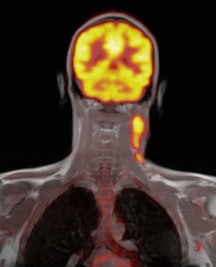

Simultaneous PET/MRI has the potential to improve patient care, reduce hospital visits, and provide new and more accurate markers for disease assessment, according to University College London researchers. Early proof-of-concept studies show the clinical performance of PET/MRI is on par with PET/CT.

Interest has been growing in the combination of PET/MRI due to the power of MRI for tissue characterization, microstructural appraisal, and functional assessment, together with new PET tracers designed to target specific metabolic processes. As a result, software-based fusion of images acquired with separate PET and MRI machines has been most common, but recently manufacturers have integrated PET and MRI hardware into a single system that acquires images from both modalities simultaneously, the U.K. researchers explained (British Journal of Radiology [BJR], 14 November 2013).

Brain imaging was one of the first applications for simultaneous PET/MRI systems because the brain is less prone to patient motion. What's more, interest is growing within the neurological community for novel radiopharmaceutical tracers to evaluate neurodegenerative and oncological disease with PET/MRI.

PET/MRI is particularly useful in imaging patients with dementia and Alzheimer's disease, because the combination of high-resolution anatomical, perfusion, and tractography MRI information with F-18 FDG or Pittsburgh Compound B (PiB) PET during a single simultaneous examination creates opportunities for improving the understanding of pathogenesis and mechanism of Alzheimer's disease, and enables early diagnosis and supports drug development.